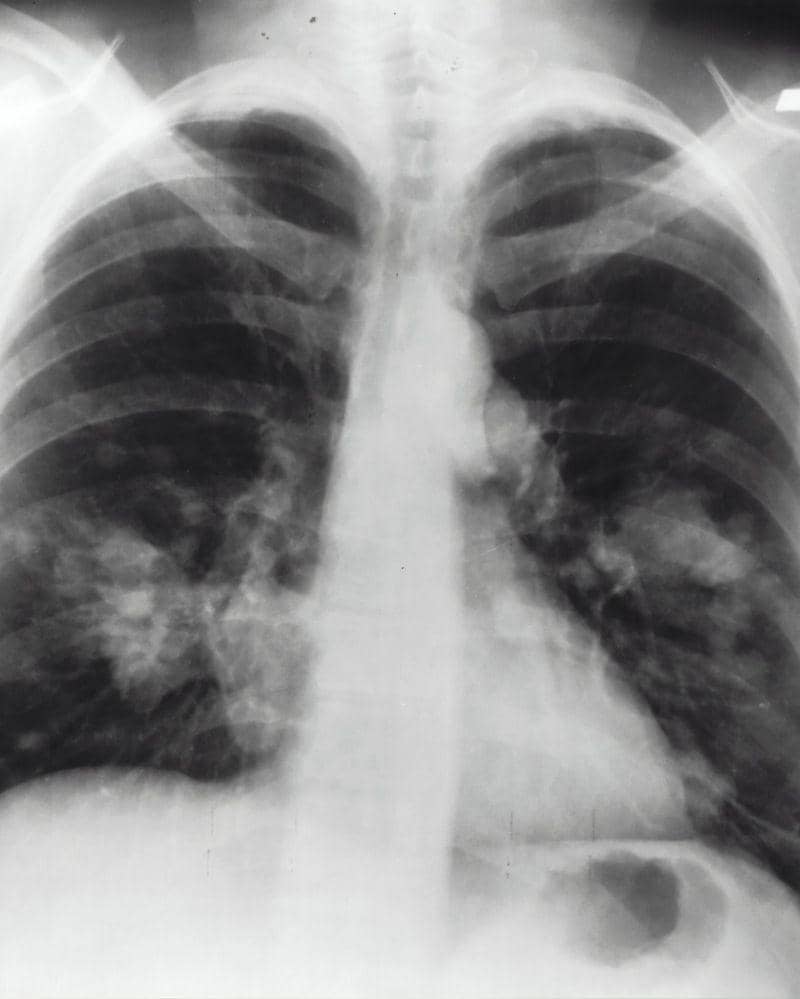

Paru-paru basah adalah istilah umum untuk sindrom gangguan pernapasan akut (ARDS). Kondisi ini terjadi ketika paru-paru diisi dengan banyak cairan dan bukannya udara. Paru-paru basah ini biasanya terjadi akibat infeksi pada paru-paru yang membuat paru-paru berisi cairan bisa darah infeksi hingga cairan cadangan dari paru-paru itu sendiri.

Kondisi paru-paru basah bisa menggambarkan beberapa penyakit, seperti pneumonia akibat infeksi bakteri atau virus (termasuk infeksi virus Corona atau Covid-19).

3. Gejala paru-paru basah yang umum terjadi

Ada beberapa gejala paru-paru basah yang bisa dikenali secara umum. Tanda yang paling sering dialami adalah flu berkepanjangan. Jika sampai mengeluarkan dahak hingga kemerahan (berdarah) jangan disepelekan ya, Ma.

Berikut adalah gejala penyakit paru-paru basah:

Paru-paru basah adalah masalah kesehatan yang perlu mendapat pemeriksaan dan penanganan dari dokter spesialis paru. Jika tidak ditangani, kondisi ini berpotensi menjadi semakin berat dan merusak paru-paru.

Beberapa orang dengan kondisi paru-paru basah atau pneumonia bisa menyebabkan nyawa tidak selamat. Pengobatan untuk penyakit ini disesuaikan dengan tingkat keparahan dan penyebabnya.